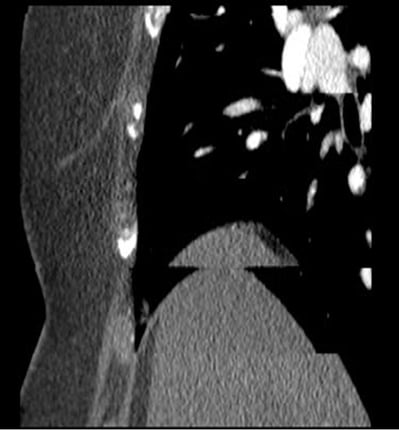

Pay particular attention to blurring. A stepped representation of the liver and diaphragm or sternum indicates breathing artifacts. This occurs primarily with mid-range CT scanners, such as 64-slice devices, which cannot capture the heart within a single heartbeat.

Example of a breathing artifact: A step in the sternum or diaphragm indicates that the patient has breathed. Image source: GE HealthCare GmbH